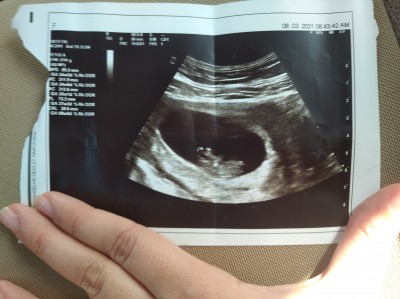

Kızlar gebelik haftası 9+5 ultrasona göre cinsiyet

tahmini yapan var mi

Bebeğin organı 12 haftada gelişmeye başlıyor 9 haftalık nasıl belli olsun

Kız gibi ramzi teorisi de öyle bildim sonucu paylaşırmısnız

Cok bilmiurm ama okuduklarımdan anladığım kadarıyla ulstason resmi bakınca en parlak ksımı plasenta olarak görünüyor 12 haftadan önceki ultrason fotosuna bakınca sağ taraftarda aslında sol olıyurmuş bebek kız eger sol da ise aslında sağmış bebek erkek miş  (ayna yöntemi) ne kadar doğru onu bilemem tahmin işte :)